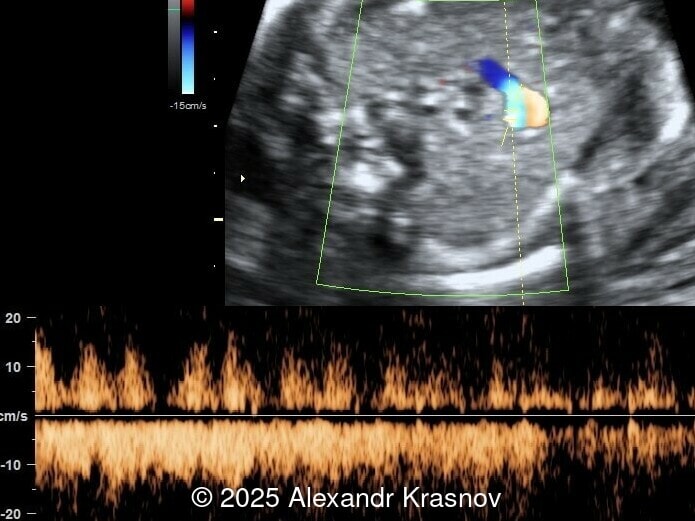

Image 4

Our ultrasound showed biometry data corresponding to 21 weeks of gestation. During echocardiography, an abnormal drainage of the pulmonary veins was detected in which the pulmonary veins drain into a venous collector linked to the superior vena cava. The four-chamber view and the three-vessel view were altered and raised suspicion of a pathology. The grayscale and color Doppler images of the four-chamber view indicate a smooth posterior wall of the left atrium, increased distance between the left atrium and the descending aorta and the absence of pulmonary veins entering the left atrium (Image 1, 2; Video 1, 2). In the three-vessel view, the diameter of the superior vena cava appears larger than that of the aorta (Image 3, Video 3). In the images of the venae cava, a significant difference is seen between the diameters of the inferior and superior vena cava with significant enlargement of the superior vena cava (Image 4, Video 4). Additionally, there is a pulmonary venous confluent chamber (“twig sign”) behind the left atrium (Image and Video 5). A vertical ascending vein connects the confluent chamber with the superior vena cava where it drains blood from the pulmonary veins (Images 6, 7; Video 6).